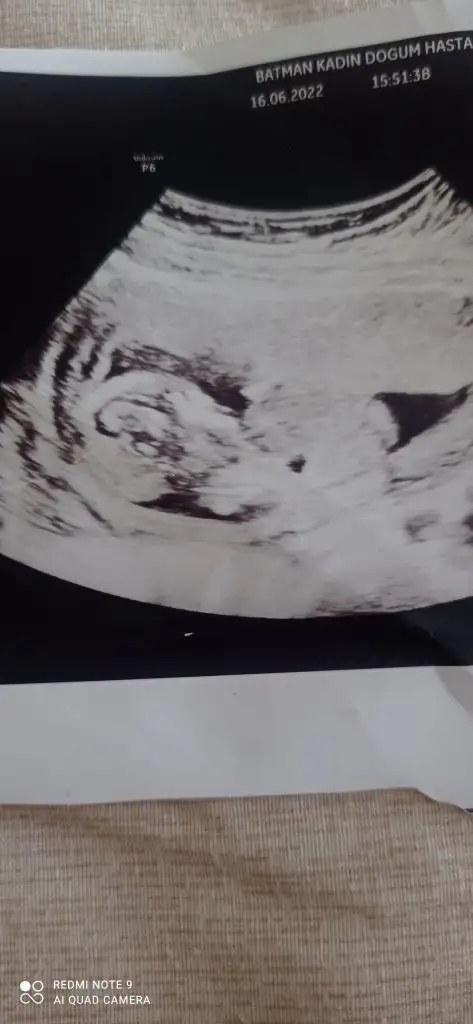

prenses gibi12+0 canım bakabilir misin

Teşekkür ederimprenses gibi